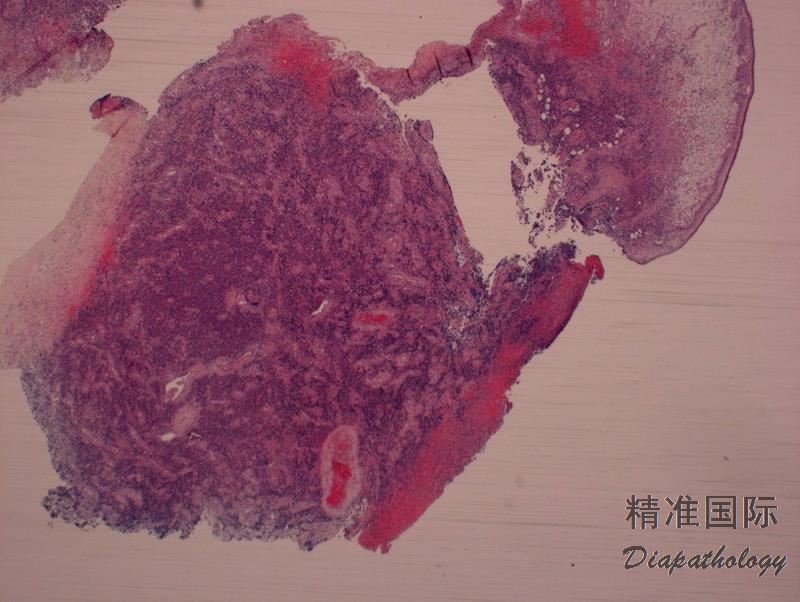

肿瘤细胞弥漫浸润,主要累及真皮层,可延及皮下组织,但有时见亲表皮浸润,特别是有 DUSP22-IRF4 病例。病灶周围可见少量背景炎性细胞,但如有溃疡,则常伴有丰富炎性细胞常(类似 LyP)。罕见病例含大量中性粒细胞(中性粒细胞富有亚型)。

多数病例肿瘤细胞呈现间变性形态(园或椭圆形核、核不规则、显著嗜伊红核仁、丰富胞质),但也可呈现多形性或免疫母样细胞形态。